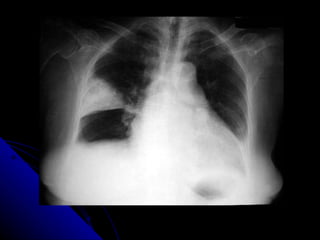

NEUMOTORAX DERECHO

HEMOTORAX POST- TRAUMA